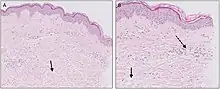

| Urticaria, lymphocyte predominant | Perivascular location. Mast cells are relatively sparse, potentially demonstrated with special stains, preferably tryptase stain. Extravasated erythrocytes are present in about 50% of the cases. No vasculitis.[14] |  Dermal edema [solid arrows in (A,B)] and a sparse superficial predominantly perivascular and interstitial infiltrate of lymphocytes and eosinophils without signs of vasculitis (dashed arrow).[15] Dermal edema [solid arrows in (A,B)] and a sparse superficial predominantly perivascular and interstitial infiltrate of lymphocytes and eosinophils without signs of vasculitis (dashed arrow).[15] |

|

| Urticaria, lymphocyte predominant | Perivascular location. Mast cells are relatively sparse, potentially demonstrated with special stains, preferably tryptase stain. Extravasated erythrocytes are present in about 50% of the cases. No vasculitis.[14] |  Dermal edema (solid arrows) and a sparse superficial predominantly perivascular and interstitial infiltrate of lymphocytes and eosinophils (dashed arrow) Dermal edema (solid arrows) and a sparse superficial predominantly perivascular and interstitial infiltrate of lymphocytes and eosinophils (dashed arrow) |

|